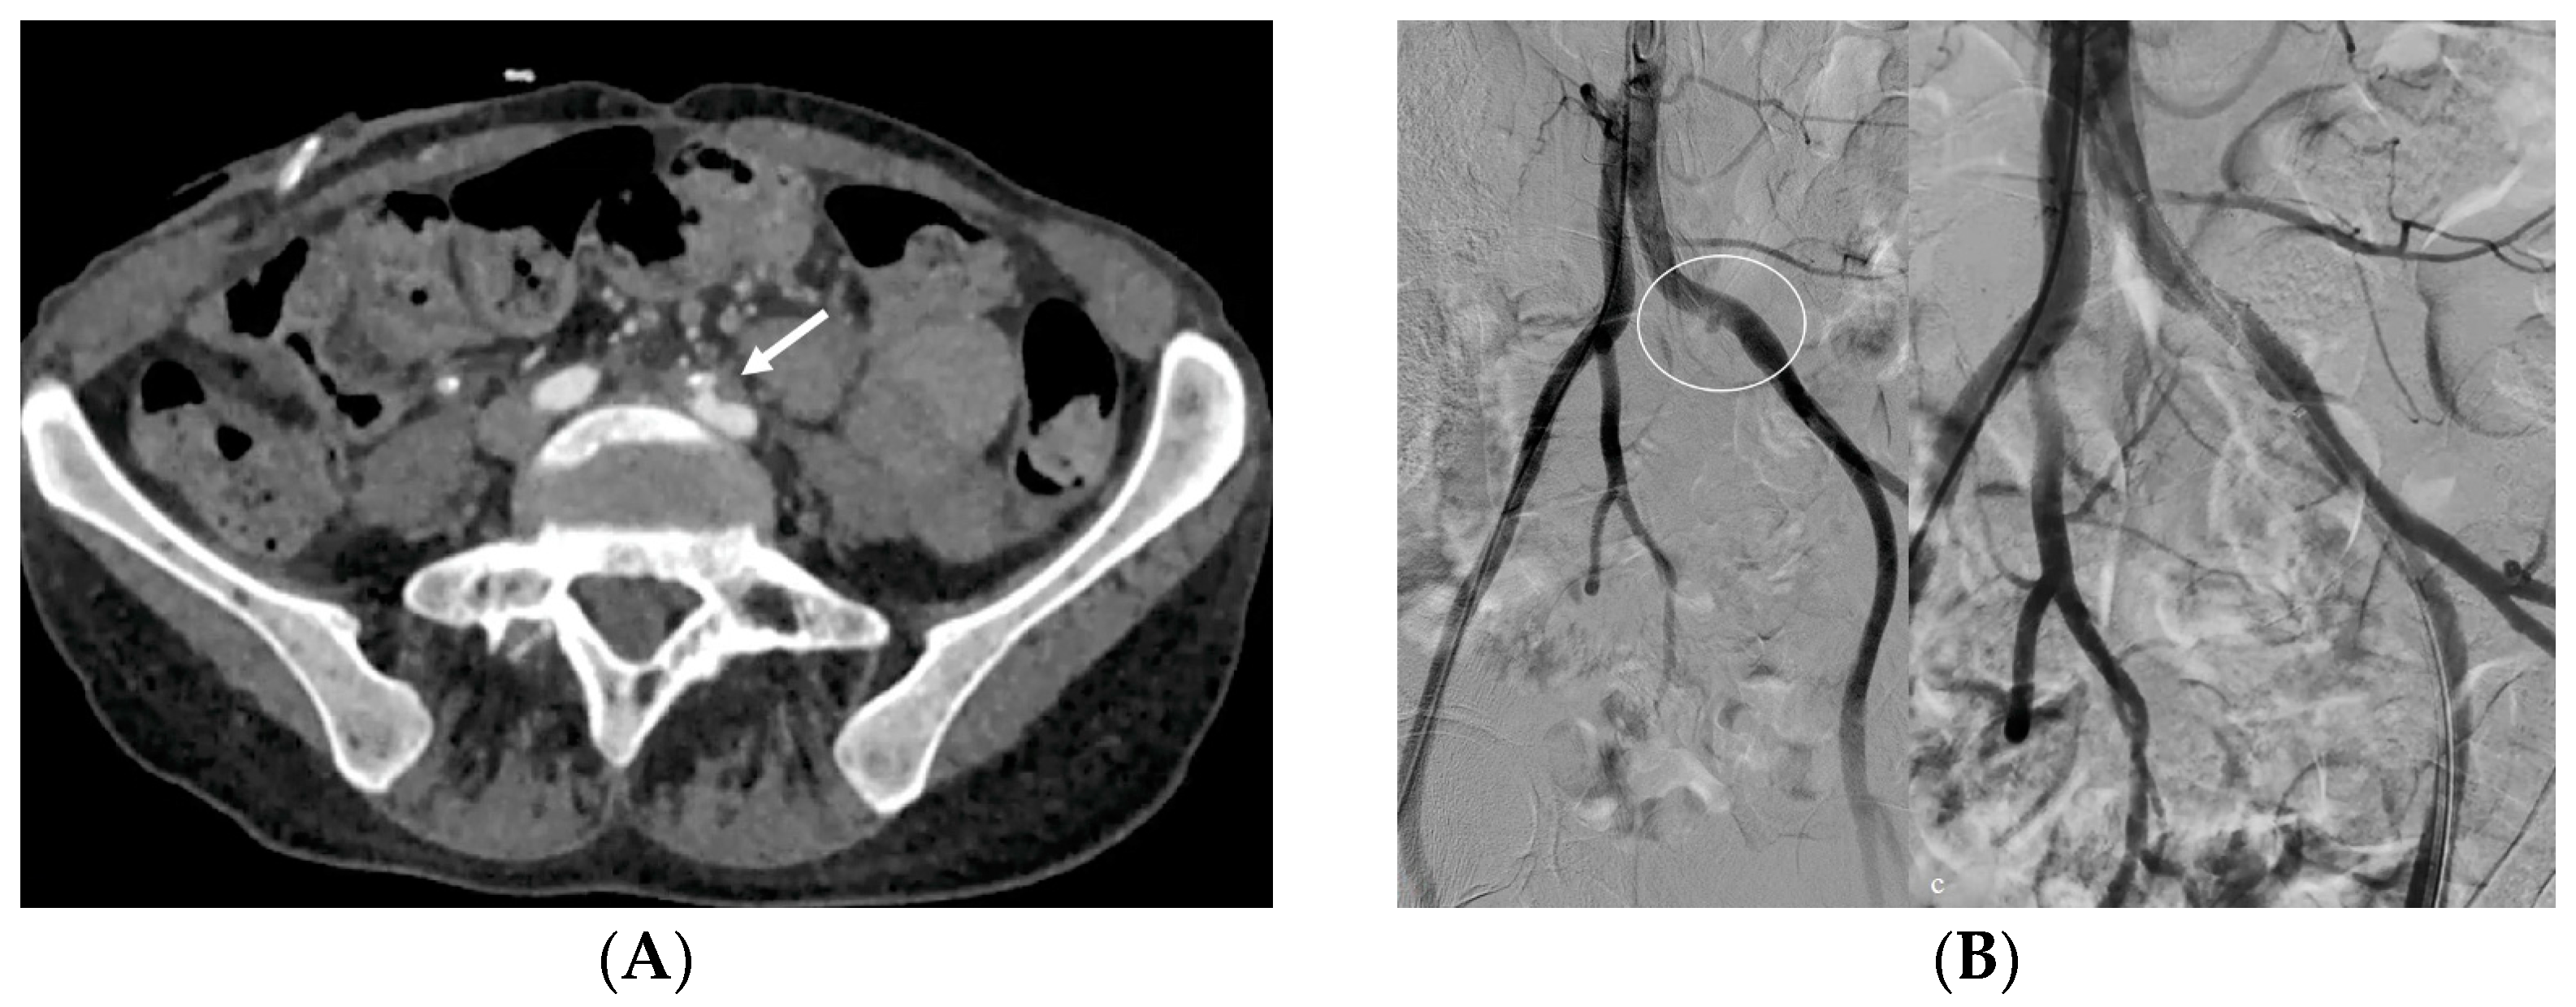

- Bleeding: The erosion of the stent into the arterial system is a rare and feared complication of ureteral stent placement, which can cause hematomas (Figure 10 and Figure 11), active bleeding, or pseudoaneurysm (Figure 12, Figure 13 and Figure 14). To avoid mortality from these complications, a high level of clinical suspicion is essential. Intermittent hematuria in a patient with a stent is typically the usual clinical scenario. However, massive hematuria and circulatory collapse can occur due to the manipulation of the ureteral stent [2,39].